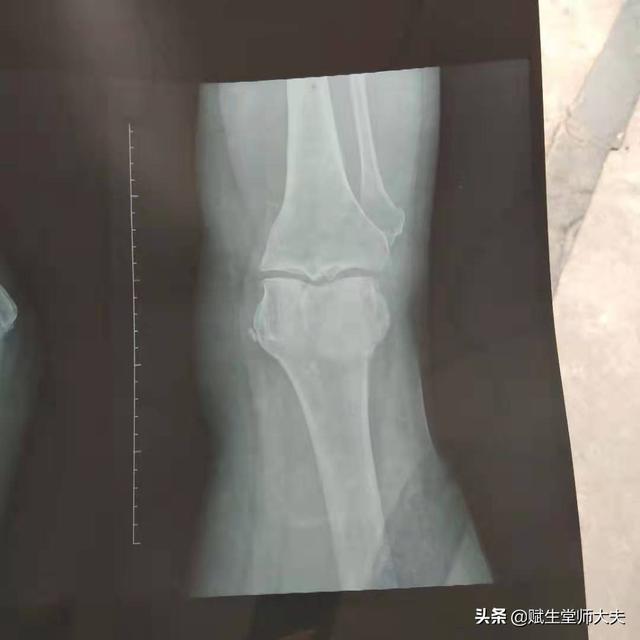

单纯的滑膜炎其实很少,很多是因为更深的原因引起的,比如说膝关节骨性关节炎、半月板损伤、交叉韧带损伤、类风湿、痛风等。急性期由于滑膜充血肿胀渗出,关节腔积液。这个时候就需要制动,比如用护膝或者支具。减少负重,扶枴行走。口服消炎止痛药物。